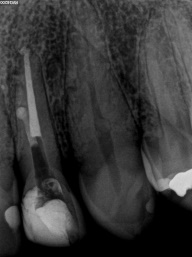

Perfurações dentarias são complicações no tratamento de canal que na maioria dos casos resulta em um prognóstico desfavorável, pois permite a entrada de microrganismos nos tecidos que envolvem o dente. Em alguns casos, devido ao seu difícil diagnóstico, acesso limitado, tempo decorrido ou tamanho da perfuração resultará em um desafio para o profissional conseguir um selamento adequado da área, sendo muito importante o conhecimento sobre o material que será empregado.